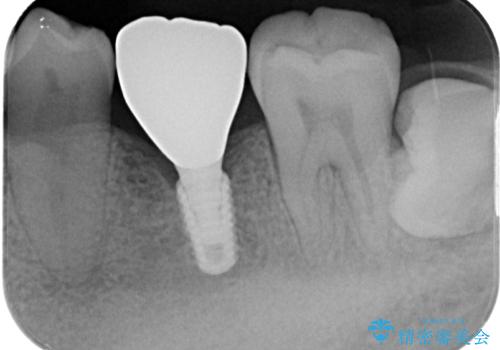

インプラント部は埋入とともに仮歯を装着し、同時に上顎奥歯の部分矯正を開始することとしました。

理想的な咬み合わせに改善した上で、インプラント補綴治療を行うこととしました。